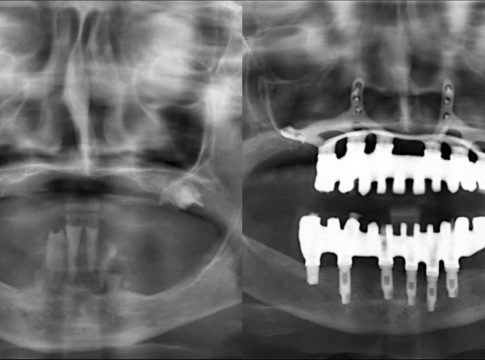

Por otro lado, los cirujanos comenzarán haciéndose una planificación digital y la elección de los materiales regenerativos que mejor se adapten al paciente. Para alcanzar el diagnóstico más preciso, la clínica utiliza tecnología 3D de escáner, con el fin de confeccionar prótesis personalizadas, que pueden ser colocadas en una única intervención.

Concretamente, un implante dental es un tornillo fabricado en titanio que se inserta en el hueso maxilar con el fin de sustituir a la raíz del diente que falta.

En los casos más complejos en los que falta la cantidad de hueso ideal, la técnica del injerto óseo es la indicada, al colocar tejido autólogo, tomado del propio paciente; o heterólogo, de otra especie, por lo general la bovina, para contar con un buen soporte del implante, sin rechazo ni reacciones alérgicas. Sin embargo, otros procedimientos que ofrece la clínica son los implantes corticales en caso de atrofia ósea extrema, los implantes cigomáticos y la técnica de elevación de seno maxilar.

Con muchas de estas técnicas se puede recurrir a la carga inmediata, es decir, colocar la prótesis fija pero provisional sobre estos implantes recién colocados.